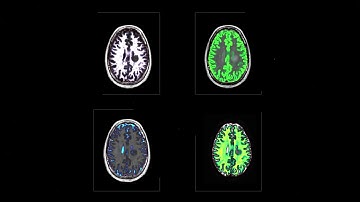

SyMRI NEURO: Why Are Quantification Values Important In Your Practice?